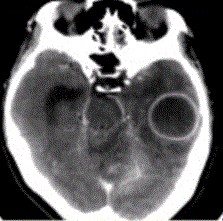

问题 患者女,26岁,头痛、低热10d余,既往有左侧慢性中耳炎病史。CT表现如下图。 初步诊断为

选项 A.脑脓肿 B.胶质瘤 C.脑血肿 D.脑梗死 E.脑囊虫

答案 A